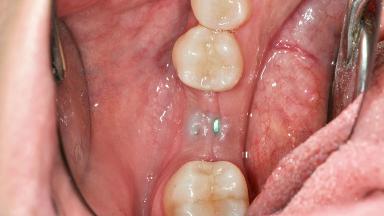

Connective-Tissue Graft to Increase the Width of the Keratinized Mucosa Around an Osseointegrated Implant

Adequate peri-implant soft-tissue thickness is essential not only for esthetic but also for functional reasons. In this case, Vincenzo Iorio Siciliano demonstrates how he achieved increased height and thickness of posterior peri-implant soft tissues to obtain a stable mucosal seal and a width of keratinized tissue favorable to toothbrushing.

The patient, a healthy 38-year-old woman, was referred for increasing the width of the keratinized tissues at the buccal aspect of dental implant 46. The site exhibited a premature-closure screw exposure caused by trauma during chewing, with inadequate keratinized tissue.